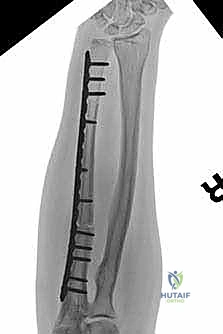

We also decide on the type and length of fixation. Plate fixation allows for standard osteosynthesis techniques and compression across the allograft-host junctions, which we believe improves healing. However, the screw holes created in the allograft are a recognized risk factor for late allograft fracture. Alternatively, intramedullary (IM) nail fixation, while potentially requiring additional incisions, generally provides stronger, more protective long-term fixation for the allograft without creating stress risers from screw holes. The challenge with IM fixation can be achieving compression at the host-graft junctions, which may impede healing. Sometimes, a combination of techniques is employed.

Sorger JI, Hornicek FJ, Zavatta M, et al. Allograft fractures revisited. Clin Orthop Relat Res 2001;382:66–74.

Late fracture of massive allografts can lead to chronic pain and loss of function. Use of intramedullary fixation and avoiding screws in the allograft may help to minimize this complication.